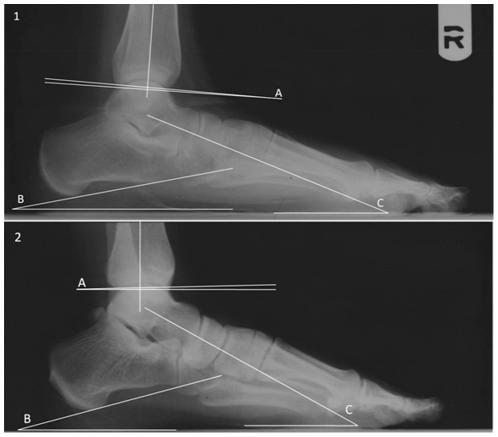

METHODOLOGY/PRINCIPAL FINDINGS: Here, we present evidence from radiographs of modern humans (n = 261) that the set of the distal tibia in the sagittal plane, henceforth referred to as the tibial arch angle, is related to rearfoot arching. Non-human primates have a posteriorly directed tibial arch angle, while most humans have an anteriorly directed tibial arch angle. Those humans with a posteriorly directed tibial arch angle (8%) have significantly lower talocalcaneal and talar declination angles, both measures of an asymptomatic flatfoot. Application of these results to the hominin fossil record reveals that a well developed rearfoot arch had evolved in Australopithecus afarensis. However, as in humans today, Australopithecus populations exhibited individual variation in foot morphology and arch development, and "Lucy" (A.L. 288-1), a 3.18 Myr-old female Australopithecus, likely possessed asymptomatic flat feet. Additional distal tibiae from the Plio-Pleistocene show variation in tibial arch angles, including two early Homo tibiae that also have slightly posteriorly directed tibial arch angles.

方法/主要发现:在这里,我们通过对 261 名现代人的 X 光片提供证据,证明矢状面上远端胫骨的设置,即胫骨弓角度,与后足足弓有关。非人类灵长类动物的胫骨弓角度向后,而大多数人类的胫骨弓角度向前。那些胫骨弓角度向后(8%)的人,距跟角和距骨倾斜角明显较低,这两个都是无症状扁平足的指标。将这些结果应用于人类化石记录表明,阿法南方古猿已经进化出了发达的后足足弓。然而,与今天的人类一样,阿法南方古猿种群在足部形态和足弓发育方面表现出个体差异,而 318 万年前的女性阿法南方古猿“露西”(AL 288-1)可能患有无症状扁平足。来自更新世的额外的远端胫骨显示出胫骨弓角度的变化,包括两个早期的人类胫骨,它们也有轻微向后的胫骨弓角度。